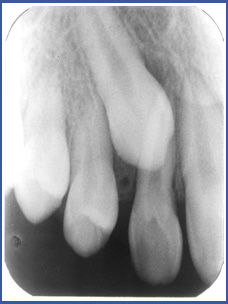

שן חלבית של ילד לפעמים "אובדת" לפני הזמן בשל עששת בשן או כתוצאה מפגיעה. אם הדבר קורה לפני שהשן הקבועה מוכנה לבקיעה, השן הסמוכה לרווח שנוצר עלולה לזוז ולסגור את המרווח שבו אמורה לבקוע השן הקבועה, ובכך ליצור חוסר מקום לבקיעת השן הקבועה. בנוסף לכך השן בלסת הנגדית עשויה אף היא לבקוע יתר על המידה אל תוך מרווח השן החסרה.

ברגע שנוצרת צפיפות במקום בו חסרה שן החלב,השן הקבועה אינה מצליחה לבקוע בצורה נכונה.

כתוצאה מכך יכולות לקרות התופעות הבאות:

- השן בוקעת בצורה עקומה או לא בוקעת כלל.

- שן הבוקעת עקום מקשה, בנוסף לכל, על אפשרות הצחצוח והשמירה על ניקיון השיניים באזור ומעלה את הסיכון לעששת.

- שן שבקעה במיקום לקוי יכולה לפגוע ביעילות הלעיסה, והיא עלולה לעבור שחיקה מהירה.

אם הבעיה לא מטופלת בשלב מוקדם על שומר מקום (שהוא מכשיר פשוט יחסית שמונע תזוזה של שיניים באזור), ייתכן שיהיה צורך בטיפול אורתודונטי מורכב בגיל מבוגר יותר.

שומר המקום הינו מתקן מתכתי קטן אשר מוכן ומותאם במיוחד לפה של הילד שלך. הוא מקובע באופן יציב בפה ויוסר כאשר השן קבועה בעמדתה הנכונה. המתקן בנוי בדרך כלל מטבעת מתכת המודבקת לשן סמוכה וחוט מתכת שמחובר אליה ונשען על שיניים סמוכות. מטרת המכשיר לייצב את השיניים הנותרות מכל צד של המרווח ולמנוע מהן לזוז לכיוון המרווח עד לבקיעת השן הקבועה לעמדתה התקינה.